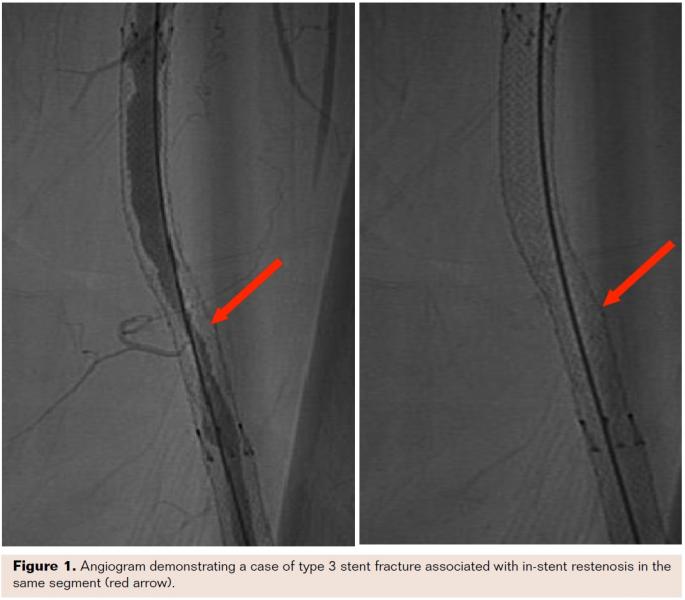

One of our patients who presented with ISR in the right SFA also had a previously implanted left SFA stent implanted 5 years prior. During angiography it was noted that the left SFA stent had a severe type 5 fracture with a pseudoaneurysm at the fracture site, with no associated restenosis or left leg symptoms (Figure 3). Another patient presented with severe thigh pain 24 hours after implantation of a nitinol self-expanding stent for prior total occlusion of the SFA. Fluoroscopy on presentation demonstrated a type 4 fracture and angiography demonstrated SFA perforation at the fracture site with active bleeding (Figure 4). This was successfully treated with a covered stent. These examples suggest that the severity and type of stent fracture may not always correlate with clinical presentation and symptoms.